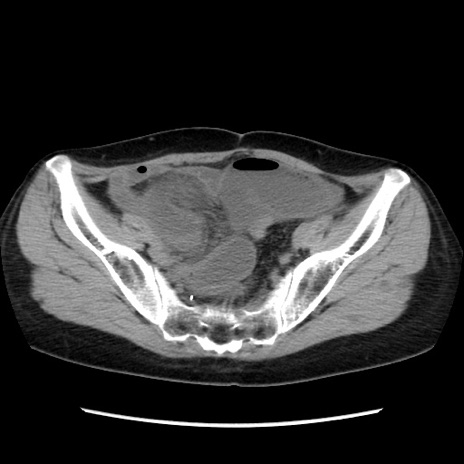

【症例】40歳代 女性

【主訴】上腹部痛、嘔気・嘔吐

【現病歴】約9時間前頃から急に上腹部痛、嘔気、嘔吐が出現。改善しないため救急要請。

【既往歴】子宮頚癌(広汎子宮全摘術、放射線療法)、腸閉塞

【身体所見】腹部:平坦、軟、腸雑音亢進、上腹部を中心に腹部全体に圧痛あり。

【データ】WBC 8400、CRP 0.03